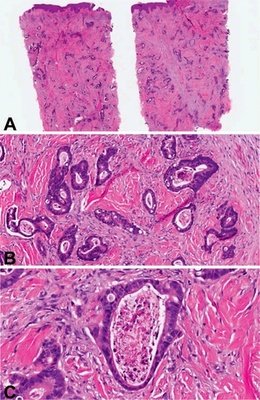

直腸腺癌屬于直腸癌的一種,是指齒狀線以上至乙狀結(jié)腸與直腸移行部之間的腺癌,占結(jié)直腸癌的75%~85%,是消化道常見的惡性腫瘤。我國直腸癌的發(fā)病率占大腸癌總發(fā)病率的60%~70%,但是病因至今仍不甚清楚。多見于40歲以上男性,分類同結(jié)腸癌。早期無明顯癥狀,癌腫增大并有潰瘍及感染時,糞便可帶血和混有黏液,排便習慣改變,伴里急后重或排便不盡感,晚期可出現(xiàn)慢性腸梗阻表現(xiàn)。當癌瘤侵犯骶叢神經(jīng)時,可有骶部劇痛,若累及前列腺或膀胱時,可引起尿頻、尿急、尿痛、尿閉或血尿等。直腸指檢、直腸鏡或乙狀結(jié)腸鏡檢查有助診斷。可手術(shù)切除,術(shù)前后可予化療,對化療敏感性差。